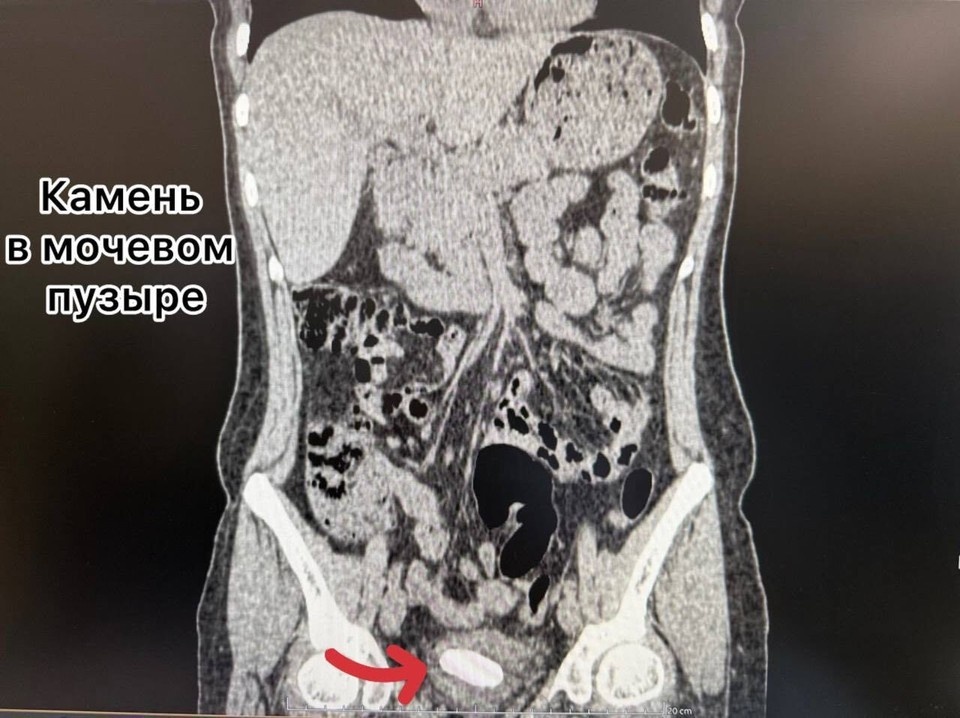

Катетер стал своего рода каркасом для отложения солей. Годами нарост становился все больше, превращаясь в плотную «каменную» структуру. В довесок крупные камни образовались и в почке, и в мочевом пузыре. Случай признали сложным в урологии, требовалась срочная операция.

Перед врачами встала непростая задача: предстояло решить три вопроса. Первый – удалить большой камень из почки, второй – раздробить и извлечь отложение из мочевого пузыря. В финале требовалось удалить прочно инкрустированный стент.

Уникальное сочетанное вмешательство проводили в рамках системы «зеленого коридора» для членов семей участников СВО. Женщине сделали один минимальный прокол в пояснице (метод перкутанной нефролитотрипсии), ультразвуком разрушили и удалили камень из почки. Параллельно через естественные пути лазером раздробили и извлекли отложение из мочевого пузыря и стент.